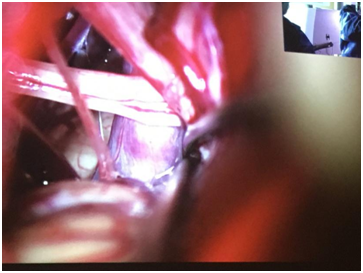

第二臺(tái)手術(shù)是微血管減壓,因?yàn)樵谑中g(shù)中間穿插講課,播放的時(shí)候已經(jīng)切開(kāi)硬腦膜,在顯微鏡和神經(jīng)內(nèi)鏡下觀察,仔細(xì)辨認(rèn)責(zé)任血管;神經(jīng)內(nèi)鏡在手術(shù)觀察有非常優(yōu)越的優(yōu)勢(shì),可以近距離、各種角度觀察。

個(gè)人感受:我覺(jué)得手術(shù)病例沒(méi)有選好,演示的患者較復(fù)雜,多根責(zé)任血管,反復(fù)、多次墊Tefflon墊片,可能會(huì)導(dǎo)致復(fù)發(fā)。

第三臺(tái)垂體瘤,左側(cè)鼻腔進(jìn)入,犁狀骨處分離黏膜,進(jìn)入右側(cè),咬骨鉗大塊咬開(kāi)蝶竇前壁骨片,暴露的非常充分,卡塞爾醫(yī)院手術(shù)也是這種風(fēng)格;他們的垂體手術(shù)暴露非常大,可以看到兩側(cè)的頸內(nèi)動(dòng)脈壓跡,使用磨鉆磨除鞍底骨質(zhì),可伸縮、隱藏刀頭的黏膜刀(我們的刀不能伸縮刀頭)切開(kāi)鞍底,黏液樣腫瘤涌出,內(nèi)鏡下清除腫瘤,再反復(fù)延伸鏡頭,確定腫瘤完全切除,鞍隔塌陷,再修復(fù)鞍底。手術(shù)順利。

個(gè)人感受:垂體腺瘤的手術(shù),國(guó)內(nèi)更加追求微創(chuàng),盡量減少創(chuàng)傷;國(guó)內(nèi)一般不會(huì)暴露兩側(cè)的頸內(nèi)動(dòng)脈壓跡。顯露的術(shù)野越大,出血也會(huì)越多,誤傷周?chē)=M織的可能性就越大。

下午的操作全部模擬上午的手術(shù),德方提供的是冰凍的尸頭,沒(méi)有使用福爾馬林,最大限度的接近手術(shù)的真實(shí)性。解剖過(guò)程中,蛛網(wǎng)膜清晰可見(jiàn),腦組織彈性良好,就像真實(shí)的手術(shù)一樣??梢钥匆?jiàn)隔壁的手術(shù)臺(tái)上,因?yàn)楸诨?,臺(tái)上滿布血水。怕引起不適,尸頭已經(jīng)做了P圖。